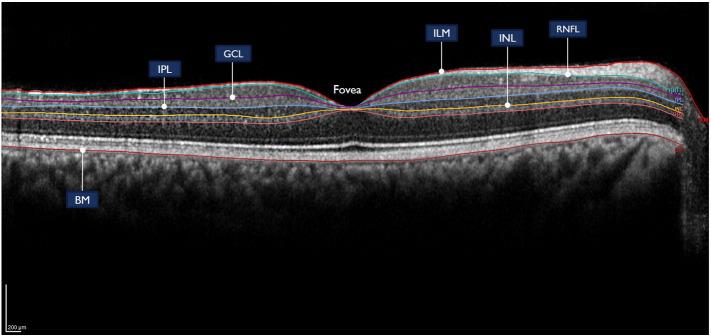

12 healthy controls, 42 multiple sclerosis (16 with optic neuritis), and 10 neuromyelitis optica participants (8 with optic neuritis) were included in this study. Optical coherence tomography assessment involved measurements of the segmented macular layers (total macular, ganglion cell layer, inner plexiform layer, and inner nuclear layer volume) and paripapillary retinal nerve fiber layer thickness. The MRI protocol included a 32-echo T2-relaxation GRASE sequence. Average myelin water fraction values were calculated within the optic radiations as a measure of myelin density.